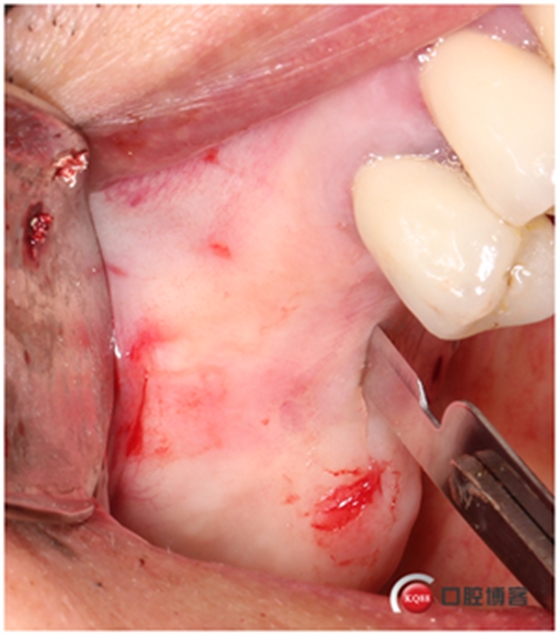

取下骨片,這才叫開窗了。

這個東西叫窗口修整鉆,頭兒是圓的且很光滑,四周是有切割功能的,用圓頭頂開上頜竇膜800-1200轉(zhuǎn)速修整窗口邊緣。

我有好的工具我任性,看看我在遠(yuǎn)中用幾秒鐘的時間再開一個窗口。

用大直徑的修整鉆修理邊緣,形成一個規(guī)則的橢圓形窗口。